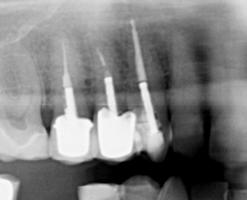

Anatomically speaking, the root canal is the area of the tooth that houses the pulp and nerve. Sometimes this part of the tooth can become infected.

When this happens, not only is the tooth painful and sensitive, the infection can also spread to other areas of the mouth as well as other teeth. The most effective way to treat this infection is root canal therapy.

Once the anaesthetic takes effect, and you are completely numb, your dentist will create a small access point in your tooth. Working through this point, the infected material will be drained out along with the pulp and any other debris. The interior of the tooth will be thoroughly cleaned out to make sure that no infection remains. An antibiotic medication may be placed inside the tooth to prevent further infection.

Your tooth will then be filled, and a cap or crown will most likely be placed. This is necessary because the structure of the tooth will be weakened, and a restoration will protect the tooth from breakage and also allow you to chew comfortably.